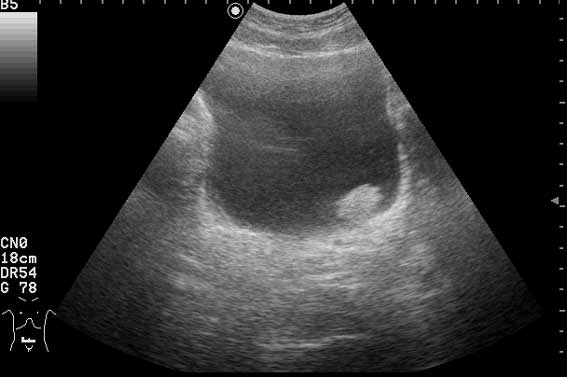

Находка у мужчины 65 лет

Ну конечно же, на представленных эхограммах - папиллярная опухоль мочевого пузыря.

Писать в заключении, что это полип - нельзя, это случай при котором руководствуются правилом - считаем опухоль злокачественной, пока не доказано обратное. Опухоль расположена над устьем левого мочеточника, нет обструкции устья и терминального отдела мочеточника (доказательство - наличие полноценного выброса мочи из устья) - что, в свою очередь, говорит против интралюминальной уретеральной опухоли.